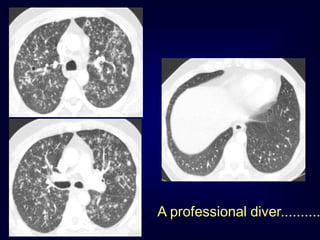

A professional diver..........

.......after cessation of smoki

Langerhans Cell Histiocytosis DifferentialDiagnosis Only small nodules Sarcoidosis, Silicosis Only cysts idiopathic Fibrosis LAM Destructive emphysema

• 139.